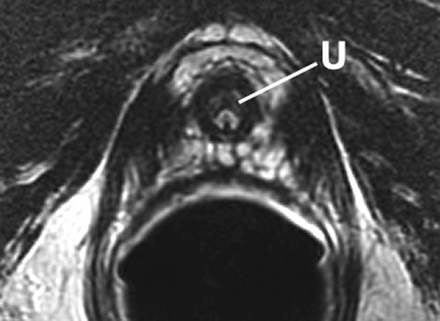

Sextant biopsies were taken routinely ≈ 1 cm apart in the parasaggital plane bilaterally, at the base, mid-gland and apical regions of the prostate, as described by Hodge et al. [1]. In addition, six further biopsies were obtained, two from the TZ and four from the lateral PZ, as depicted in Fig. 1. The TZ biopsies were taken at the level of the mid-gland where the TZ was most prominent. The lateral PZ biopsies were taken by positioning the probe just medial to the lateral edge of the prostate at the base and mid-gland regions bilaterally, as described by Chang et al. [8]. This method generally allowed any area of DRE abnormality or suspicious hypoechoic lesion noted on TRUS to be incorporated into the biopsy protocol. All patients underwent the same biopsy strategy with no variance for gland size. Biopsies were obtained using an 18 G core-biopsy needle mounted on a spring-loaded automatic biopsy gun. All patients were placed in the left lateral decubitus ('knee-chest') position and all were examined with no prior bowel preparation. The procedure was generally well tolerated and no patient required intravenous sedation or narcotic analgesia. All TRUS was undertaken by the same operators (D.R.G. and N.S.), either personally, or when supervising a higher urological trainee.